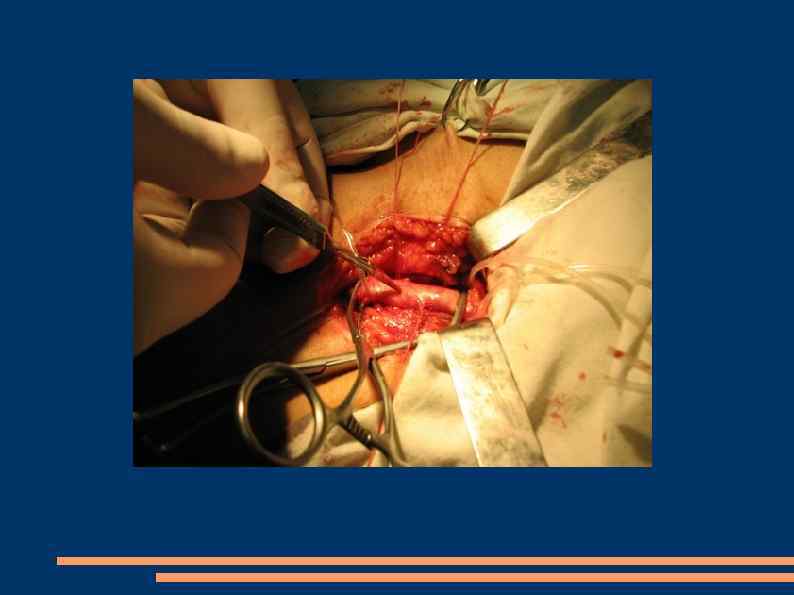

Открытая эндартерэтомия